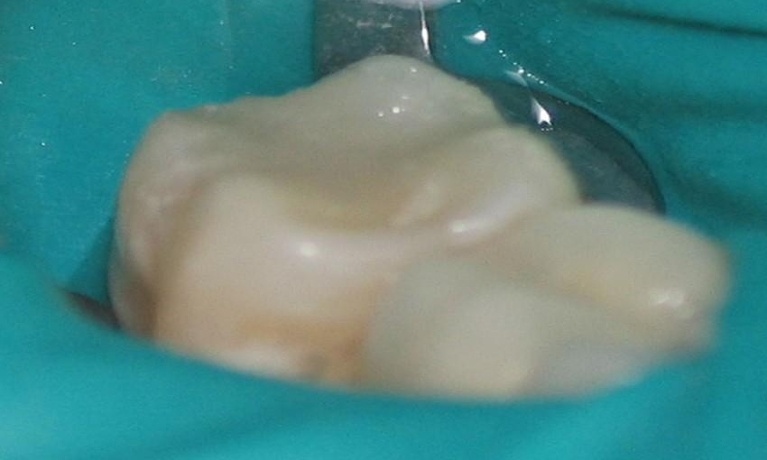

Are you considering dentistry at Michael J Nelson DDS? If so, we’d like to invite you to browse our Smile Gallery. Our dental team can improve your oral health and help you attain the attractive smile you’ve always wanted.